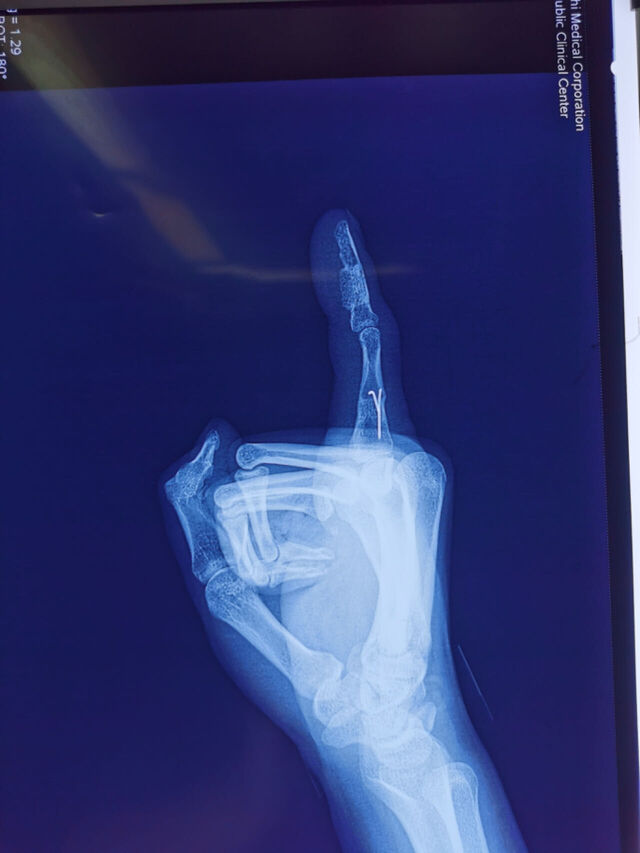

今天的环指再造

微信图片_20231008195909.jpg 微信图片_20231008195912.jpg 微信图片_20231008195906.jpg 微信图片_20231008195903.jpg 微信图片_20231008195839.jpg 微信图片_20231008195829.jpg 微信图片_20231008195945.jpg 微信图片_20231008195939.jpg